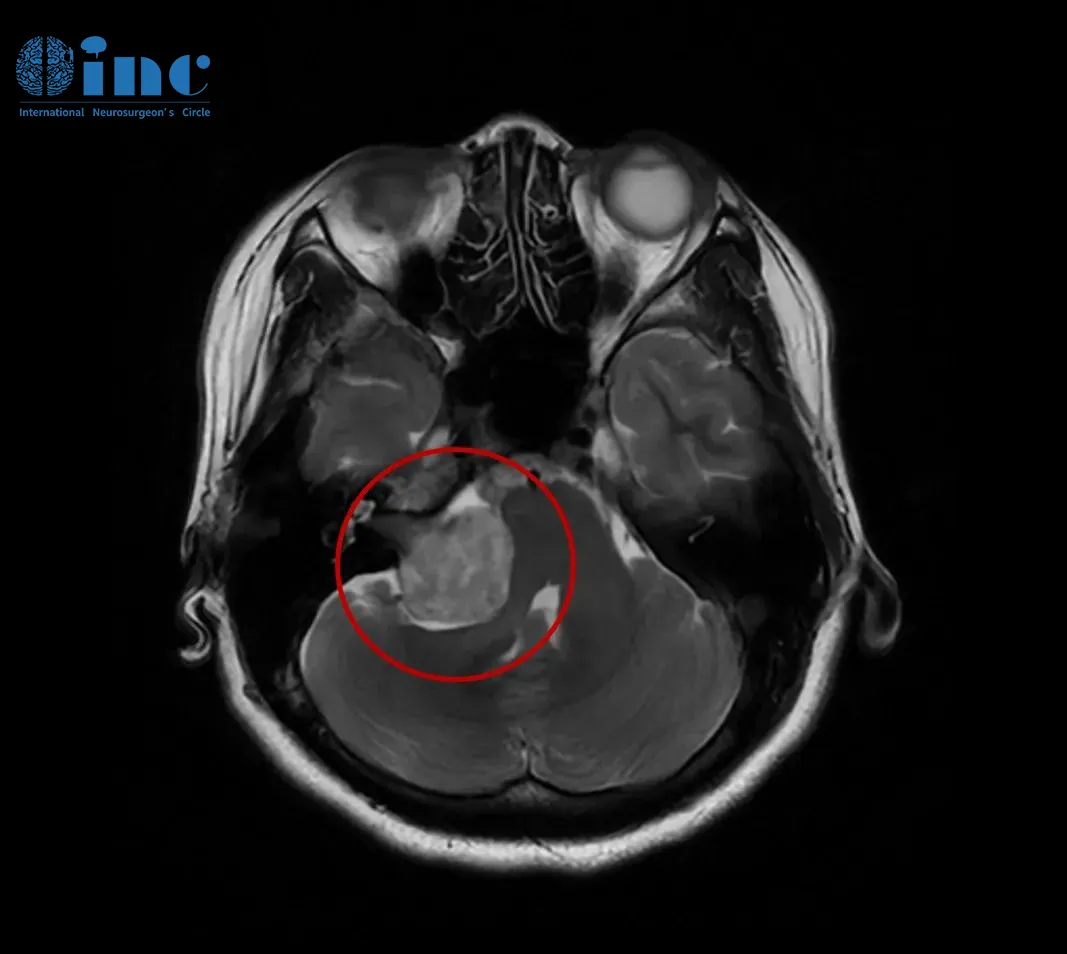

这次,她做了头颅核磁共振(MRI)检查,结果终于揭示了病因——右侧CPA区前庭神经鞘瘤。肿瘤最大直径约35毫米(包括内听道内的部分),已经压迫到脑干,导致桥脑及右侧桥臂受压,四脑室变形。

一切准备就绪后,巴教授针对肿瘤的具体位置、形态特点,手术采用适合患者具体情况的个体化手术入路,术中使用神经电生理监测和MRI辅助,保证神经功能、重要脑组织不受损伤,在显微镜下完成并确认肿瘤全部切除。

术后两年MRI检查结果更让人满意:肿瘤被完全切除,没有任何复发迹象。如今她的面部功能完全恢复,面部对称,右侧面神经功能良好。